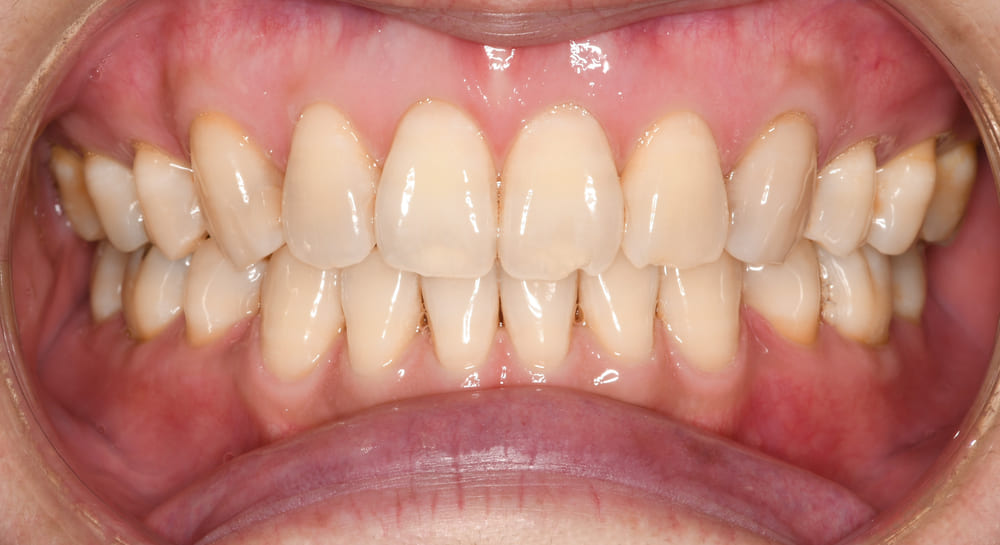

口腔内の写真です。まずは正面です。

上下顎の正中線も顔面正中を基準にぴったりと合っています。

また個々の歯の位置異常が適切に整えられていることがお分かりいただけると思います。